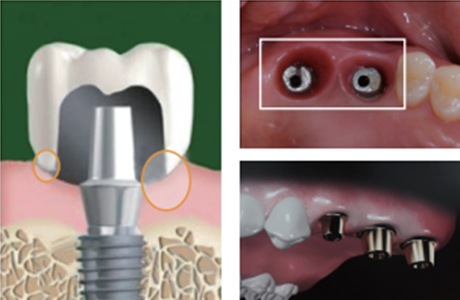

Abutment (지대주)

임플란트 뿌리와 머리를 연결하는 부위입니다.

Abutment(지대주)의 형태

기성 Abutment뿌리와 보철의 크기를 고려하여 만들어진 기성 형태의 어버트먼트

기성 Abutment뿌리와 보철의 크기를 고려하여 만들어진 기성 형태의 어버트먼트보편적으로 흔히 쓰이고 있는 기본 형태의 어버트먼트로 개인에게 맞추어진 형태는 아니기 때문에 사용함에 있어 불편함이 동반될 수 있습니다.

맞춤형 Abutment환자의 개인 구강구조를 고려하여 만들어진 개인 맞춤(커스텀) 형태의 어버트먼트

맞춤형 Abutment환자의 개인 구강구조를 고려하여 만들어진 개인 맞춤(커스텀) 형태의 어버트먼트환자 개개인의 구강구조에 맞춘 커스텀형 어버트먼트로 구강구조에 딱맞는 형태이기 때문에 사용함에 있어 불편이 덜하며 틈이 없는 밀착력으로 음식물 끼임 등의 문제도 적습니다.